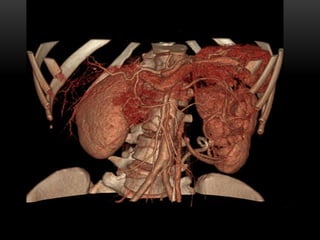

PROYECCIÓN DE MÁXIMA INTENSIDAD MIP

• Selecciona un rango de cortes bidimensionales

• Permite realzar las estructuras con mayor atenuación, facilita una visualización rápida y

efectiva de estructuras densas ( vasos contrastados y huesos)

• Este procedmiento se emplea principamente para examinar v. sang contrastados

PROYECCIÓN DE MÁXIMAINTENSIDAD MIP • Selecciona un rango de cortes bidimensionales • Permite realzar las estructuras con mayor atenuación, facilita una visualización rápida y efectiva de estructuras densas ( vasos contrastados y huesos)

• 62.

• Este procedmientose emplea principamente para examinar v. sang contrastados